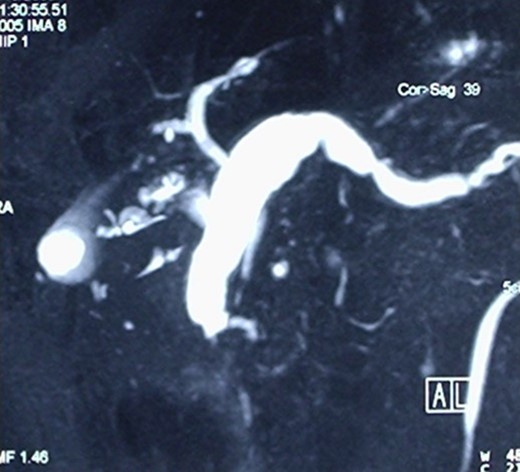

The operative specimen showed a normal thin choledocus (incannulated with a probe) cephalad to a fragile inhomogeneous area corresponding to the tumor (Fig. 4) and an enormously dilated pancreatic duct (held by the forceps) (Fig. 5).

The operative specimen showing a normal thin choledocus (incannulated with a probe) cephalad to the tumor.